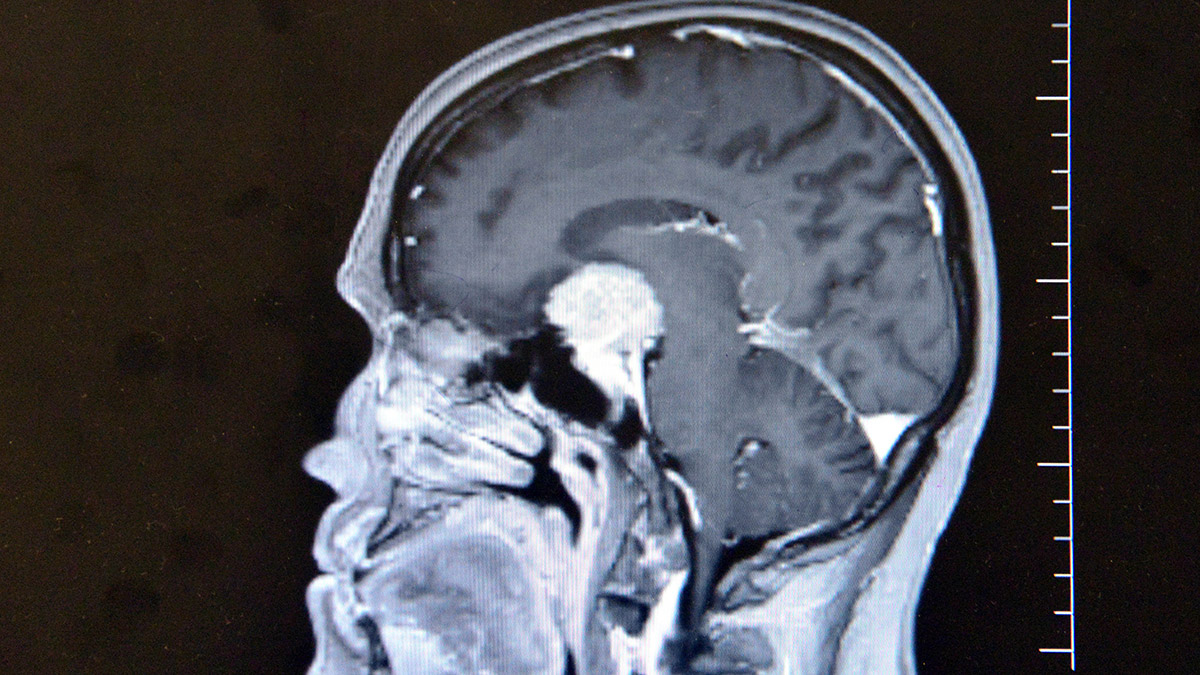

Kahramanmaraş’ta görme kaybı başlayan Ayşe Gül’ün (56) beyninde ceviz büyüklüğünde tümör tespit edildi. Beyin ve Sinir Cerrahi Öğretim Üyesi Doç. Dr. İdiris Altun, beyindeki tümörün olduğu bölgede görülmesinin milyonda 1 olduğunu söyledi.

Altun tarafından yapılan muayene ve tetkiklerde Gül’ün beyninde ceviz büyüklüğünde tümör olduğu ve gözündeki sorunun tümörden kaynaklandığı tespit edildi. Altun, Ayşe Gül’e acilen ameliyat olması gerektiğini ancak tümörün ana şah damarlarının olduğu bölgede olmasından dolayı ölüm riskinin yüzde 80, yaşaması halinde ise felç kalma ihtimalinin de çok yüksek olduğunu söyledi.

“Hastamız görme şikayetiyle ilgili birçok yere gitmiş ancak hastalıkla ilgili bir teşhis konulamamış. En son çekilen filminde ana şah damarlarını tamamen saran, görme sinirini tamamen kapatan, solunumla hayat merkezinin önünde geniş bir kitle olması üzerine hasta tarafıma geldi. Hastayı değerlendirdikten sonra endoskopik yöntemle kamera eşliğinde burundan girerek ceviz büyüklüğünde, 3,5 santim genişliğindeki kitleyi almaya karar verdik.

Hastamız gayet iyi rahat. Beynin orta yerinde taban bölgesinde dediğimiz, 3,5 santim ebadında, ceviz büyüklüğündeki tümörümüz solunum hayat merkezinin önünü kaplaması ve oraya doğru ilerlemesi, sağ ana damarlara doğru ilerleyip tamamen içerine alması ve hipofiz bezini alttan yukarı doğru sarması, bu ebada ulaşması milyonda bir oranda gözükür. Biz bu tümörü, burundan girilerek endoskopik yöntemle tamamen ana damarlara herhangi bir zarar vermeden çıkarttık.”